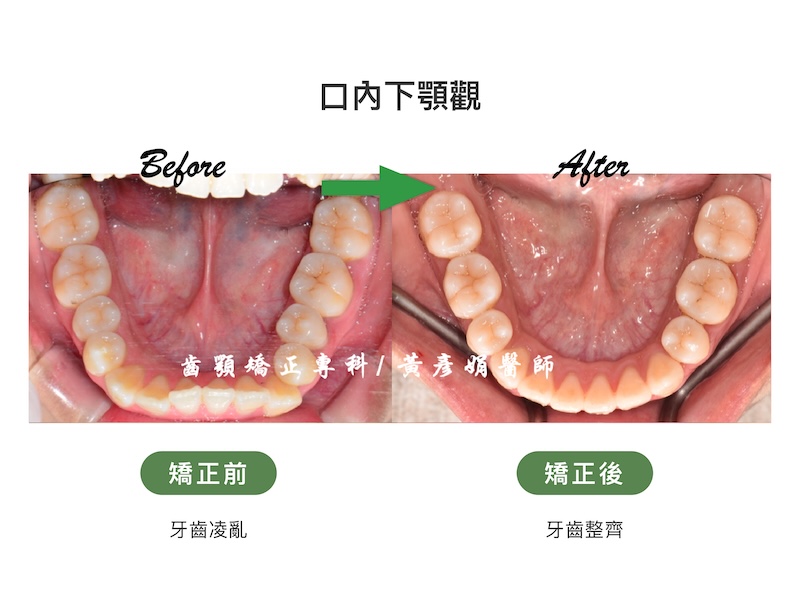

牙齒矯正前:骨暴/暴牙/嘴唇閉不起來/牙齒凌亂/牙齒擁擠

- 主訴:暴牙、嘴唇閉不起來、牙齒亂

佩佩的牙弓有比較擁擠的情況,以及合併上下齒列前凸,因此需要空間同時排整齊及後退牙齒。透過上顎和下顎各拔兩個小臼齒,並用骨釘加強後退力量,以達到良好的美觀和功能。

牙齒矯正前後咬合變化